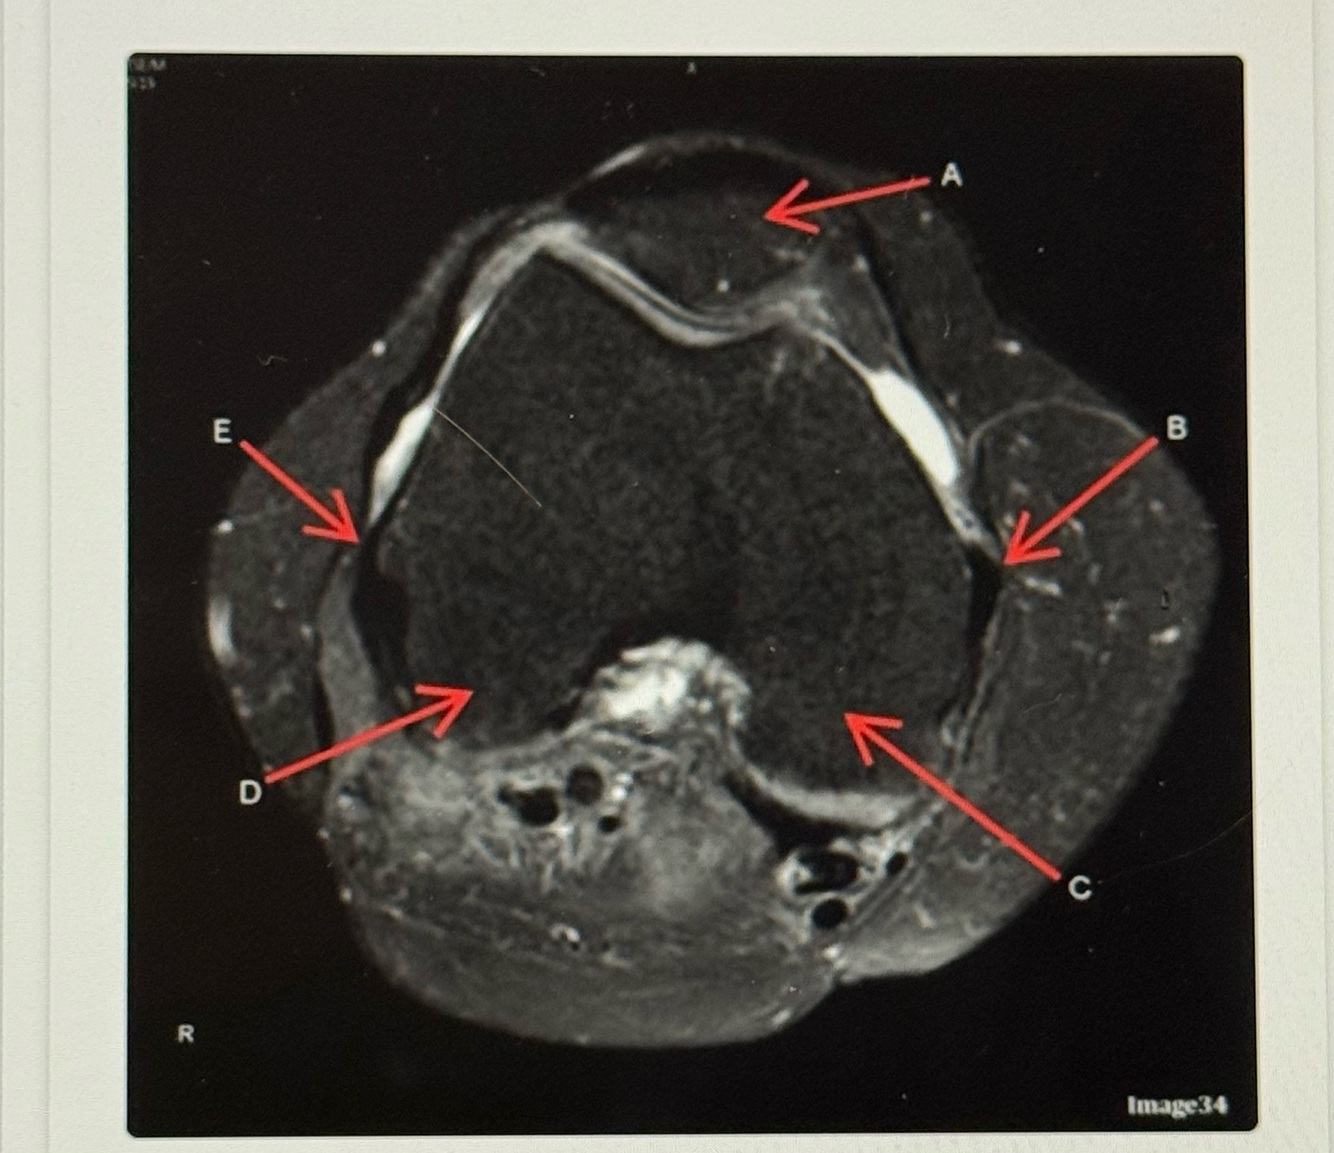

20

Q

Letter D points to the

A

Lateral femoral condyle

21

Letter C points to the

Medial femoral condyle

22

Letter B points to the

Medial

Collateral ligament (MCL)

23

Letter A points to the

24

Letter E points to the

Lateral collateral ligament (LCL)

25

Medial collateral ligament (MCL)

26

Letter A is pointing to the

27

Medial Meniscus

28

Tibeal plateau

29

Lateral meniscus

30

Letter F points to the